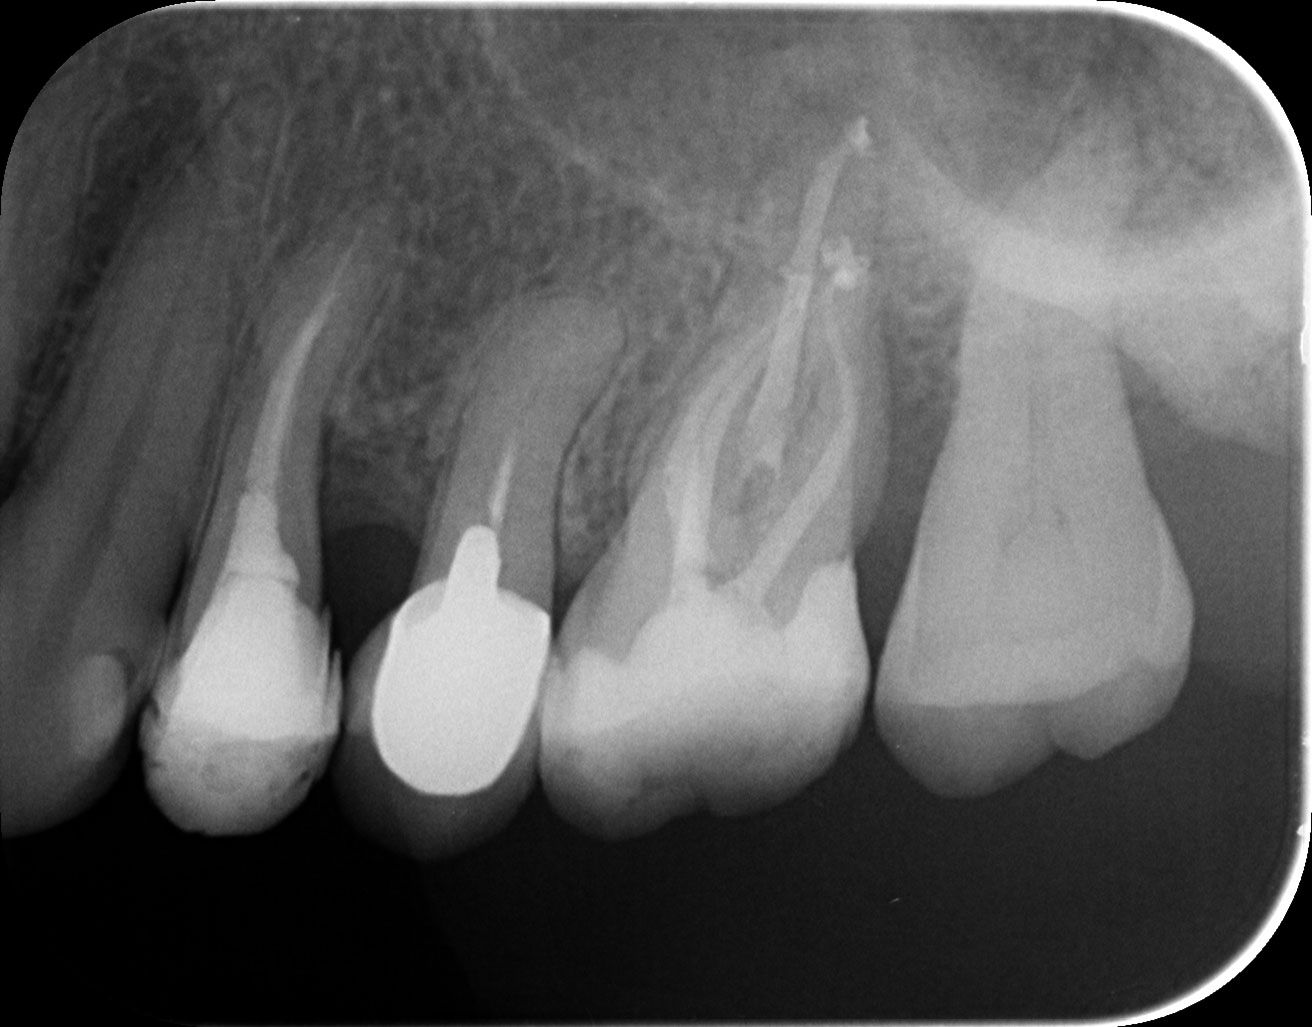

Dantų kanalų gydymas